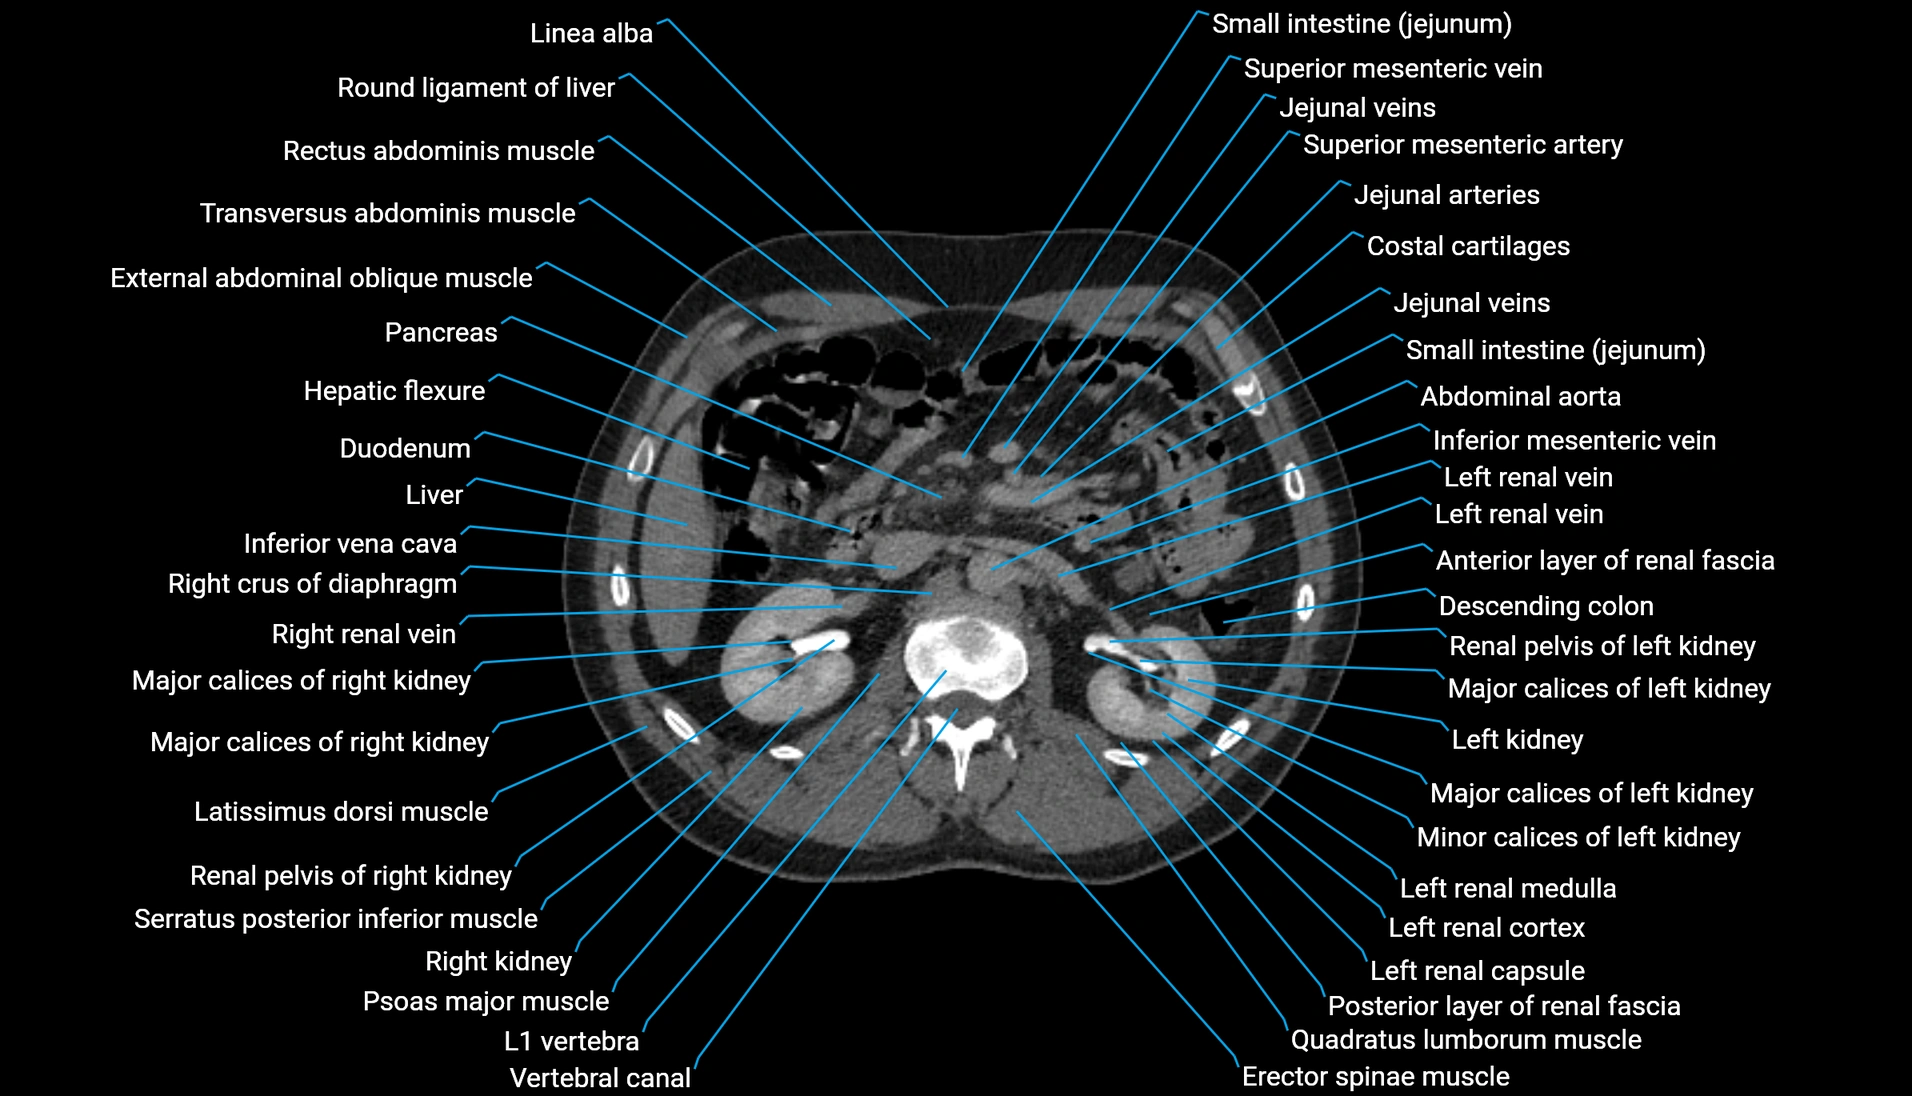

CT Appearance

Non-contrast CT:

-

Demonstrates cortical bone of acetabular rim in excellent detail

Detects fractures, dysplasia, retroversion, or bony overcoverage (pincer impingement)

3D reconstructions used in preoperative hip surgery planning

CT VRT 3D image

CT image